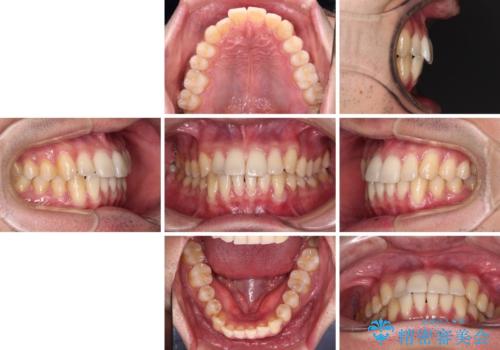

ワイヤー装置での上下前歯の部分矯正

- 上下前歯のデコボコを気にして来院された患者様です。

部分矯正は咬み合わせが不安定になったり、スペースができてしまったりと、適用となる患者様は極めて限られますが、こちらの方はスムーズに治療を終えることができました。